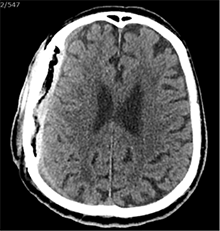

Po 2 savaičių pacientas rastas parkritęs kieme. Buvo matyti kraujuojanti žaizda. Pacientas pakartotinai hospitalizuotas į Neurochirurgijos skyrių. Atlikus GKT, nustatyta 25 mm storio hipodencinė juosta virš dešiniojo smegenų pusrutulio ir 8 mm vidurinių smegenų struktūrų dislokacija (VSD) į kairę (3 pav.). Įtariant lėtinę SDH dešinėje pusėje, pacientas reoperuotas, atliekant rekraniotomiją. Operacijos metu ant kietojo smegenų dangalo (KSD) rasta fibrino, jis pašalintas. Pravėrus KSD, rastas drumstas turinys, nesant aiškių pūlių, ir stora kapsulė. Gausiai praplauta šiltu fiziologiniu tirpalu subduraliai. Kaulinis lopas grąžintas (4 pav.). Po operacijos pacientas pradėjo skųstis stipriu galvos skausmu, tapo vangus. GKT pakartota. Įtarta empiema, nustatyti oro tarpai subduraliai, galvos smegenų VSD – 6 mm. Praėjus 12 dienų po antros operacijos, pacientas operuotas pakartotinai. Operacijos metu atlikta rekraniotomija. Epiduriniame ir subduriniame tarpuose rasta pūlių ir fibrino. Pūliai ir fibrinas pašalinti, paimtas bakteriologinis pasėlis. Žaizda gausiai praplauta šiltu fiziologiniu tirpalu. Kaulinis lopas negrąžintas, minkštieji audiniai susiūti (5 pav.). Po operacijos paciento būklė stabilizavosi. Bakteriologiniame pasėlyje negausiai užaugo E. coli, jautri ampicilinui. Nesant teigiamo efekto gydant ampicilinu, dar 2 savaites pacientui skirta gentamicino. Praėjus 3 savaitėms po trečios operacijos, pacientas perkeltas į slaugos ligoninę palaikomojo gydymo.

3 pav. Prieš antrąją operaciją (25 mm storio hipodencinė juosta virš dešiniojo smegenų pusrutulio, esant 8 mm dislokacijai į kairę; įtarta lėtinė SDH dešinėje)